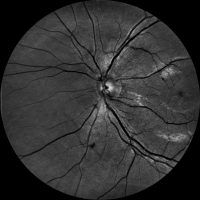

Dzięki technologi SLO – Scanning Laser Ophthalmoscope, podczerwieni oraz wiązki zielonego laseru, jesteśmy wstanie wykonać bardzo dokładny zrzut dna oka, dzięki czemu wykryjemy praktycznie każde zmiany w gałce ocznej. W realizacji takiego skanu nie potrzebne jest zakroplenie oka co znacznie usprawnia nam diagnostykę pod katem szybkości badania czy samopoczucia osoby poddanej tejże czynności. Badanie ma na celu wykrycie zmian w oku jak: jaskra, zaćma, zatory żylne, męty, retinopatie cukrzycową czy AMD(zwyrodnienie plamki żółtej), Pełna wizyta obejmuje: